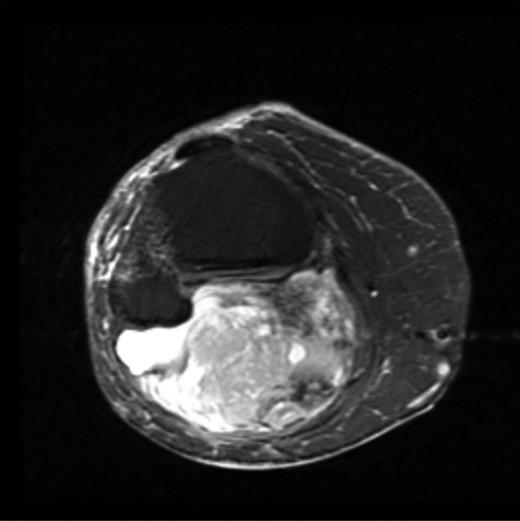

The MRI scan of the right knee (Figs 2 and 3) with gadolinium-enhancement showed a large mass lesion in the posterior aspect of the right knee extending into the popliteal fossa and into the upper third of the right leg having appearance of bursal pathology. Post gadolinium images showed evidence of circumferential rim enhancement but no internal enhancement indicating the presence of a fluid filled lesion. The mass (Figs 4 and 5) measured ∼8.39 × 6.14 × 12.72 cm and was seen between semimembranosus and biceps femoris muscles. There was no evidence of any infiltration of either the sciatic nerve or the popliteal vessels. A likely diagnosis of complicated synovial cyst with a differential diagnosis of haematoma was reported and a provisional diagnosis of Baker's cyst was established.

Post gadolinium-enhanced MRI image showing circumferential lesion.